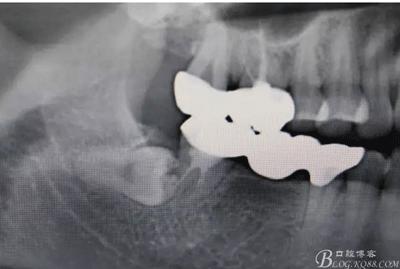

圖2.局部影像放大:48與47牙根 有部分重疊,顯示48牙冠位于47牙根的頰側(cè)或者舌側(cè),增加了損傷47全瓷牙的風(fēng)險(xiǎn)。